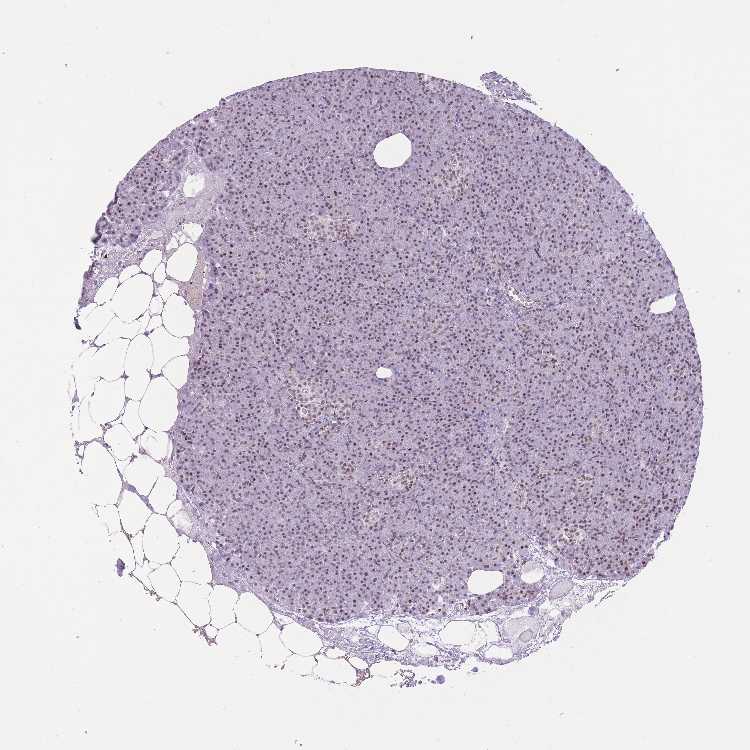

TBC1D26